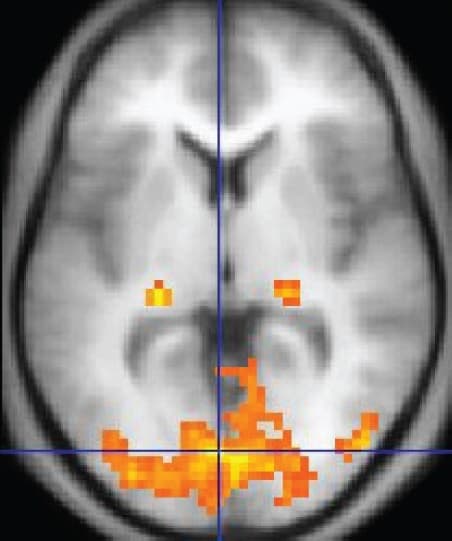

This work has considerable ramifications for the understanding of the origin of the signals detected with the current functional brain imaging techniques used in neurological and psychiatric research (see for example Magistretti et al, Science, 283: 496 497, 1999). He is the author of over 100 articles published in peer-reviewed journals.